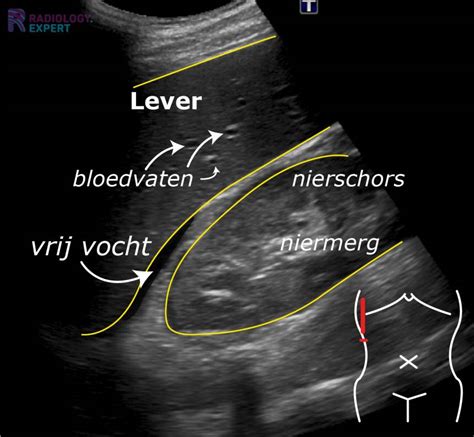

Tijdens een pre-natale echografie wordt een ovariumcyste zichtbaar als een met vocht gevulde massa die niet op de middenlijn ligt bij een vrouwelijke foetus. Het kan soms lastig zijn om deze cyste te onderscheiden van een dundarmcyste of een urachuscyste, wat een uitstulping is van het foetale plaskanaal. Een cyste met een diameter van 2 cm wordt doorgaans als normaal of fysiologisch beschouwd.

Na de geboorte wordt de cyste echografisch gemonitord. Meestal neemt de grootte van de cyste snel af in de eerste drie levensmaanden. Door middel van vier- tot zeswekelijkse echografie-evaluaties wordt de evolutie nauwlettend gevolgd. Bij hevige, onverklaarbare pijn, moet men alert zijn op mogelijke bloedingen in de cyste of een draaiing van de cyste of eierstok. Een echografie kan uitsluitsel geven of deze complicaties aanwezig zijn.